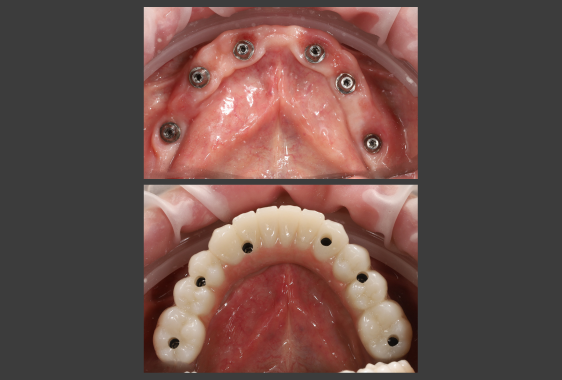

Хірургічний шаблон являє собою персоналізовану 3D-навігаційна капу з отворами для імплантів. Він виготовляється персонально під пацієнта та фіксується в ротовій порожнині протягом імплантації. Трафарет задає точний вектор, глибину, кут нахилу імпланту, забезпечуючи йому довгострокову стабільність і функціональність.

- Цифрове планування імплантації. Створюється віртуальна модель розміщення імплантів із точним розрахунком глибини, кута, позиції. Проводиться цифрова примірка майбутніх коронок – візуалізація майбутньої усмішки на екрані монітора.

- точне встановлення імплантів забезпечує надійну фіксацію, отже – стабільність протезів;